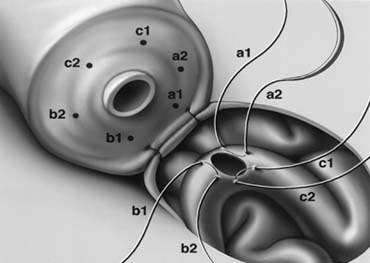

Microsurgical End-to-Side Intussusception Technique

This method, also known as the triangulation technique,43 has gained increasing popularity among microsurgeons over the conventional end-to-end and end-to-side vasoepididymostomy.4,44,45,46 When the level of epididymal obstruction is clearly demarcated by the presence of markedly dilated tubules proximally and collapsed tubules distally, the site at which the anastomosis should be performed is readily apparent (Figs. 19 and 20). The vas deferens is drawn through an opening in the tunica vaginalis and secured in proximity to the potential anastomotic site in the epididymis with two to four interrupted sutures of 6-0 polypropylene placed through the vasal adventitia and the epididymal tunica (Fig. 21). Six microdots are placed on the cut surface of the vas in an identical fashion to that described for vaso-vasostomy (Fig. 22). Three 10-0 double-armed nylon sutures are placed in the epididymal tubule in a triangular fashion (Fig. 23). The needles are not pulled through but left in situ, creating a triangle of needles. A generous opening is made in the epididymal tubule in the center of the triangle created by the three needles. The three needles are then pulled through (Fig. 24). A glass slide is touched to the fluid exuding from the opening in the epididymal tubule and mixed with human tubal fluid media, covered with a cover slip and examined by the surgeon using the separate bench microscope under 400-power magnification. If sperm are present (whether motile or not) the decision is made to proceed with the anastomosis. Sperm are aspirated into micropipettes first (Fig. 25) and expressed into human tubal fluid media and sent for cryopreservation if motility is observed. After abundant sperm have been aspirated into micropipettes and cryopreserved, the six needles are passed inside out the vas deferens exiting through the six previously placed microdots in the order indicated (Fig. 26). Each pair of sutures is then sequentially tied. Tying of these sutures intussuscepts the epididymal tubule into the vas lumen (Fig. 27). This creates a water-tight closure. In addition, the flow of epididymal fluid from the epididymal tubule into the vas deferens tends to plaster the edges of the epididymal tubule against the mucosal walls of the vas deferens, further helping create a leakproof closure. The second layer of the anastomosis is completed using interrupted 9-0 nylon sutures to secure the epididymal tunica to the vasal sheath (Fig. 28).

Fig. 21. Preparation for vasoepididymostomy. The 6-0 sutures approximate the posterior lip of vasal adventitia to lower edge of opening tailored in the epididymal tunica.

Fig. 22. As in vasovasosotomy, the use of microdots on the cut surface of the vas can enhance precision in suture placement.

Fig. 23. Three 10-0 nylon sutures are placed on the epididymal tubule in a triangulation fashion. To avoid leaking of fluid, which will lead to collapse of the tubule and difficult placement of subsequent sutures, the needles are left in place. In addition, accidental cutting of the sutures is avoided when opening the tubule with a sharp microknife.

Fig. 24. Position of sutures in the epididymal tubule once the tubule is opened.

Fig. 25. Once the presence of sperm in the epididymal tubule has been confirmed, epididymal fluid is aspirated by capillary action into micropipette for cryopreservation.

Fig. 26. The six needles are passed inside-out the vas deferens exiting through the six microdots.

Fig. 27. Tying the sutures intussuscepts the epididymal tubule into the vas lumen.

Fig. 28. Closure of the second layer with 9-0 sutures.

Two-Stitch Longitudinal Variation of the Intussusception Technique

A two-stitch longitudinal variation of the intussusception technique has been recently described (Fig. 29).47 The two-stitch intussusception technique is much easier to perform with superior success rate.47,48 For anastomoses to very small epididymal tubules such as those found in the caput or to the efferent ductules,45 the three-stitch triangular technique may be impossible. This technique is currently our preferred method for all vasoepididymostomies. With this method, four microdots are marked on the cut surface of the vas deferens and two parallel sutures are placed in the distended epididymal tubule but not pulled through. After the fluid is tested for sperm and aspirated into micropipettes for cryopreservation, the four needles are passed inside-out the vas deferens and tied. The anastomosis is completed as described previously.

Fig. 29. Two-needle longitudinal intussusception vasoepididymostomy. The longitudinal placement of needles allows for a longer tubular incision, resulting in a larger opening.